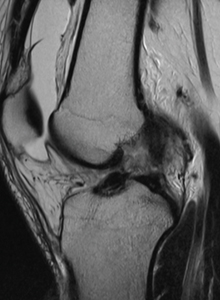

BEFORE